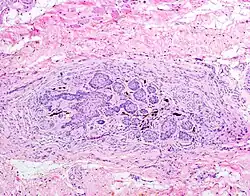

![]() The juxtaoral organ of Chievitz is composed of nests of benign squamoid epithelium closely associated with multiple nerve bundles. The deep location and squamous appearance can histologically mimic invasive squamous cell carcinoma. (Hematoxylin and Eosin stained section, 100x magnification) | |

The juxtaoral organ in humans is a small longish structure (12.7 mm (half an inch) in length, 1–2 mm in diameter), situated medially to the medial pterygoid muscle. The organ consists of a central ramified cord of epithelial parenchyma, embedded in connective tissue particularly rich in nerve fibers and sensory receptors. Close relations exist between epithelial cells and nerve endings. Histochemically, the parenchyma displays a characteristic pattern of various enzymes. Sporadically, epithelial follicles containing colloidal material can be found. The organ is surrounded by a dense, perineurium-like connective tissue.